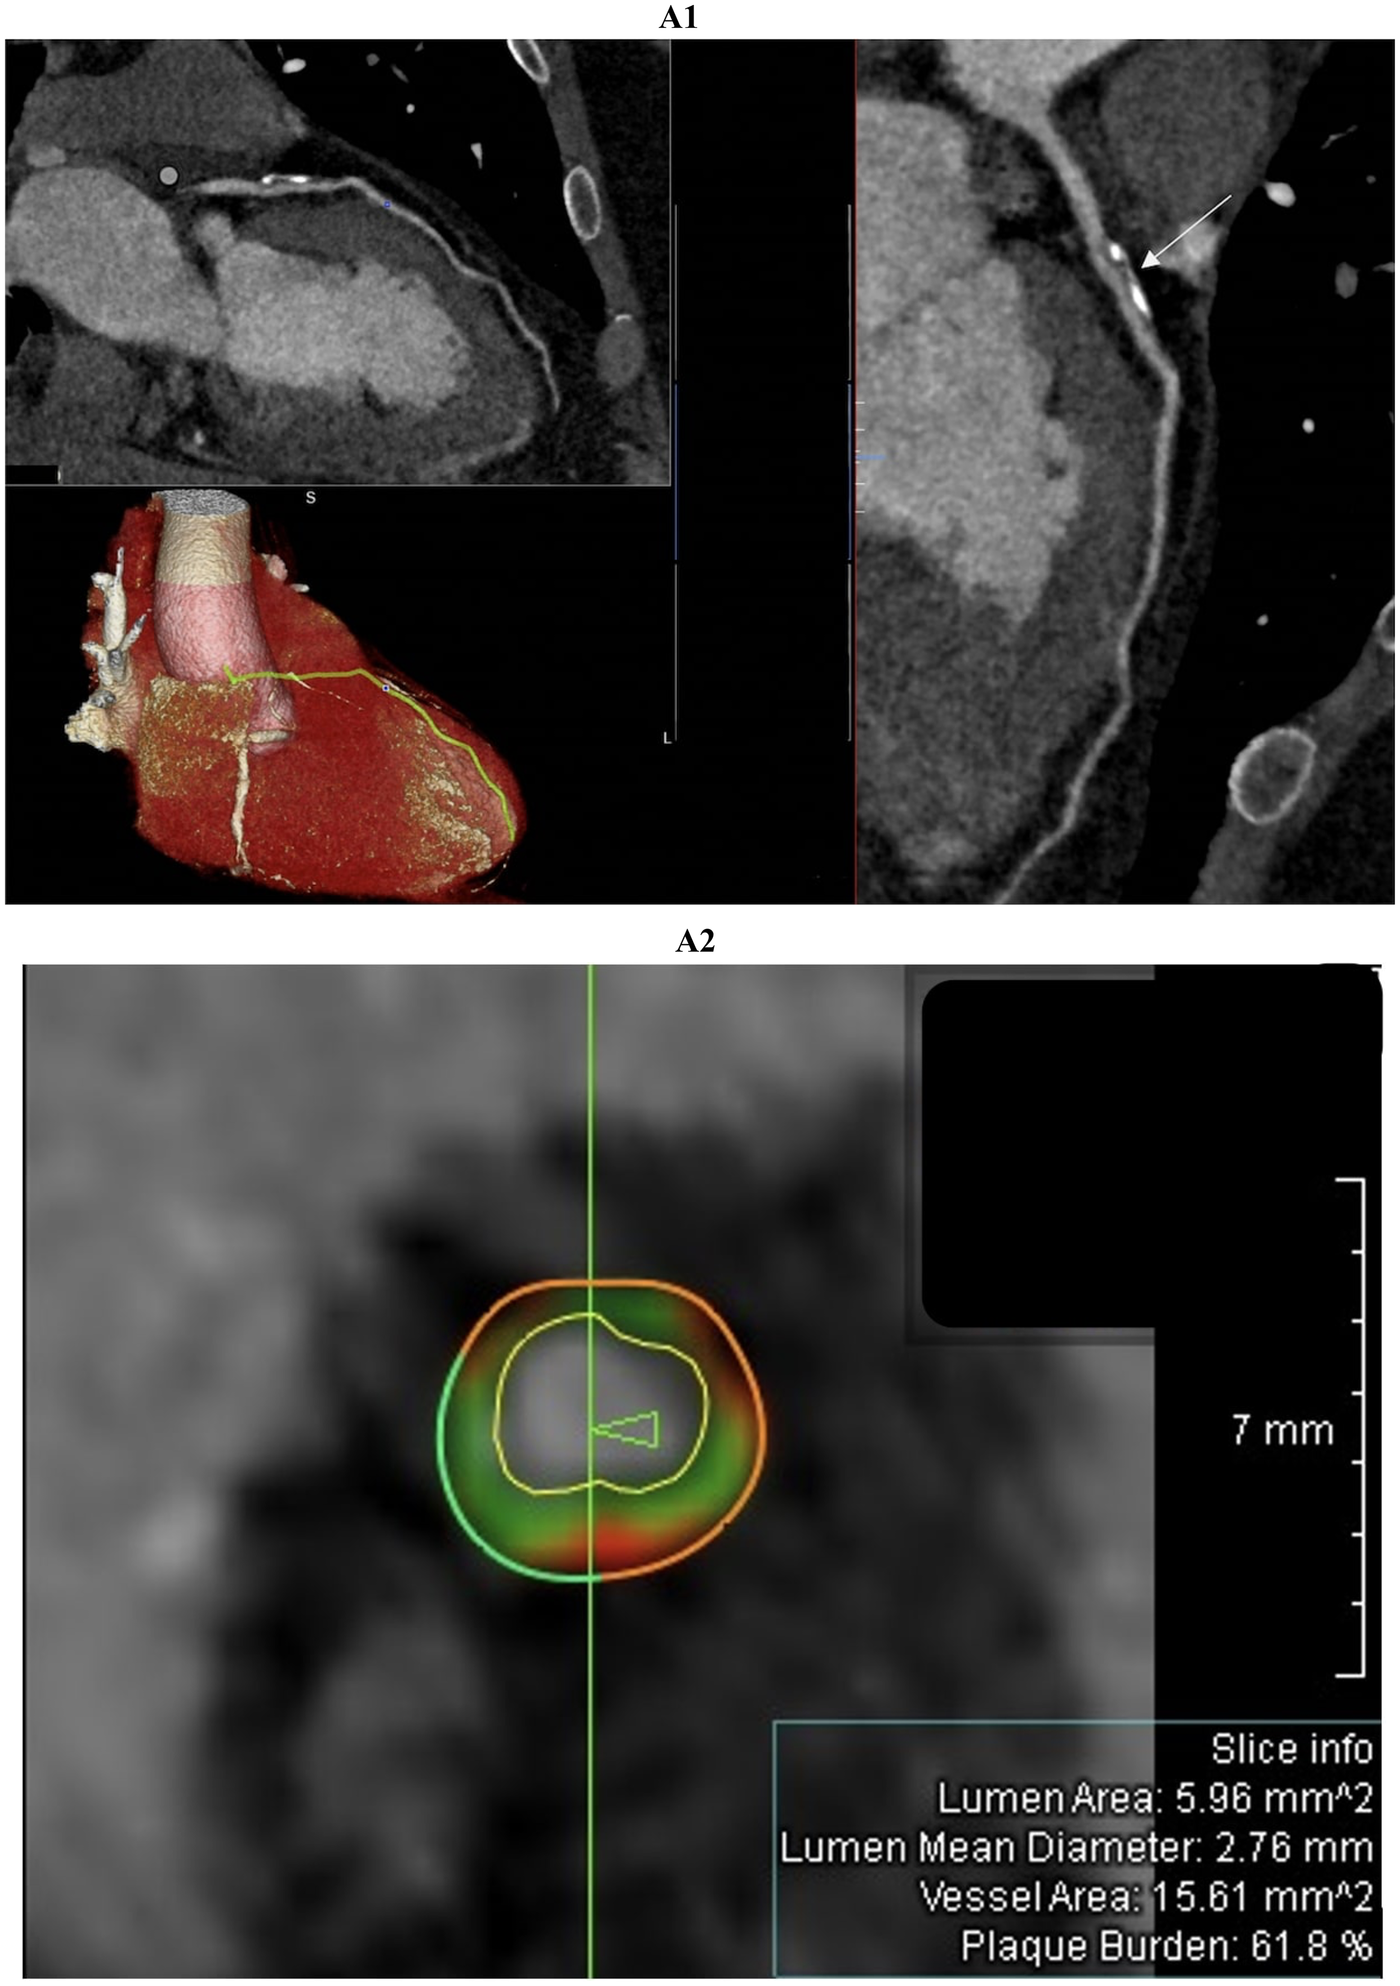

Figure 2

Comprehensive coronary artery evaluation using coronary computed tomography angiography (CCTA) with advanced image reconstructions and quantitative plaque analysis was performed in a 51-year-old male patient admitted with suspected acute myocardial infarction with non-obstructive coronary arteries (MINOCA). The curved multiplanar reconstruction (figure 2A1, top left panel and large right panel) offers a detailed longitudinal view of the left anterior descending (LAD) artery, clearly delineating the vessel lumen and wall morphology. The proximal LAD segment reveals an extensive, eccentrically located plaque predominantly composed of calcific tissue. This lesion exhibits typical features of positive remodeling without causing significant luminal narrowing or flow limitation. The three-dimensional volume-rendered image (figure 2A1, bottom left panel) shows the heart and coronary arteries with the LAD artery highlighted in yellow, facilitating spatial comprehension of plaque localization and vessel trajectory from the left main coronary artery to the apex. Cross-sectional imaging (figure 2A2), indicated by the white arrow in figure 2A1, combined with quantitative coronary plaque analysis identifies a high-risk plaque with positive remodeling. The green vertical line marks the exact location of the cross-section shown in figure 2A2 and the arrow indicates the slice orientation relative to the vessel. This concentric plaque includes dark green fibrous tissue, light green fibrofatty tissue, and red necrotic core, which are characteristic of high-risk features. The external vessel wall contour is partly dark green, representing fibrous tissue, and partly red, indicating the necrotic core. The internal vessel wall contour, shown in light green, corresponds to fibrofatty tissue. The white boundary inside the vessel marks the lumen contour, defining the blood flow space. Lumen area (5.96 mm2), mean diameter (2.76 mm), vessel area (15.61 mm2), and plaque burden (61.8%) are reported in the slice info box.

Coronary CT angiography was performed following invasive coronary angiography that excluded stenosis greater than 50%, as the patients continued to experience chest pain and still demonstrated abnormal findings on their electrocardiogram (ECG). CCTA showed no atherosclerosis in 16 patients; the remaining 5 (including 3 with MINOCA) had non-obstructive (<50 percent) lesions in the left anterior descending artery, often accompanied by minor irregularities in the circumflex or right coronary arteries. High-risk plaque features—positive remodeling, low-attenuation core, spotty calcification, or napkin-ring sign—were present in 3 MINOCA patients (Figure 2). Late iodine enhancement (LIE) performed 7−10 min after contrast administration most frequently revealed subepicardial or mid-wall iodine uptake; subendocardial enhancement, primarily in the territory of the left anterior descending artery (specifically the basal anterior interventricular septum and the basal anterior wall of the left ventricle) was observed in the same 8 patients with MINOCA.